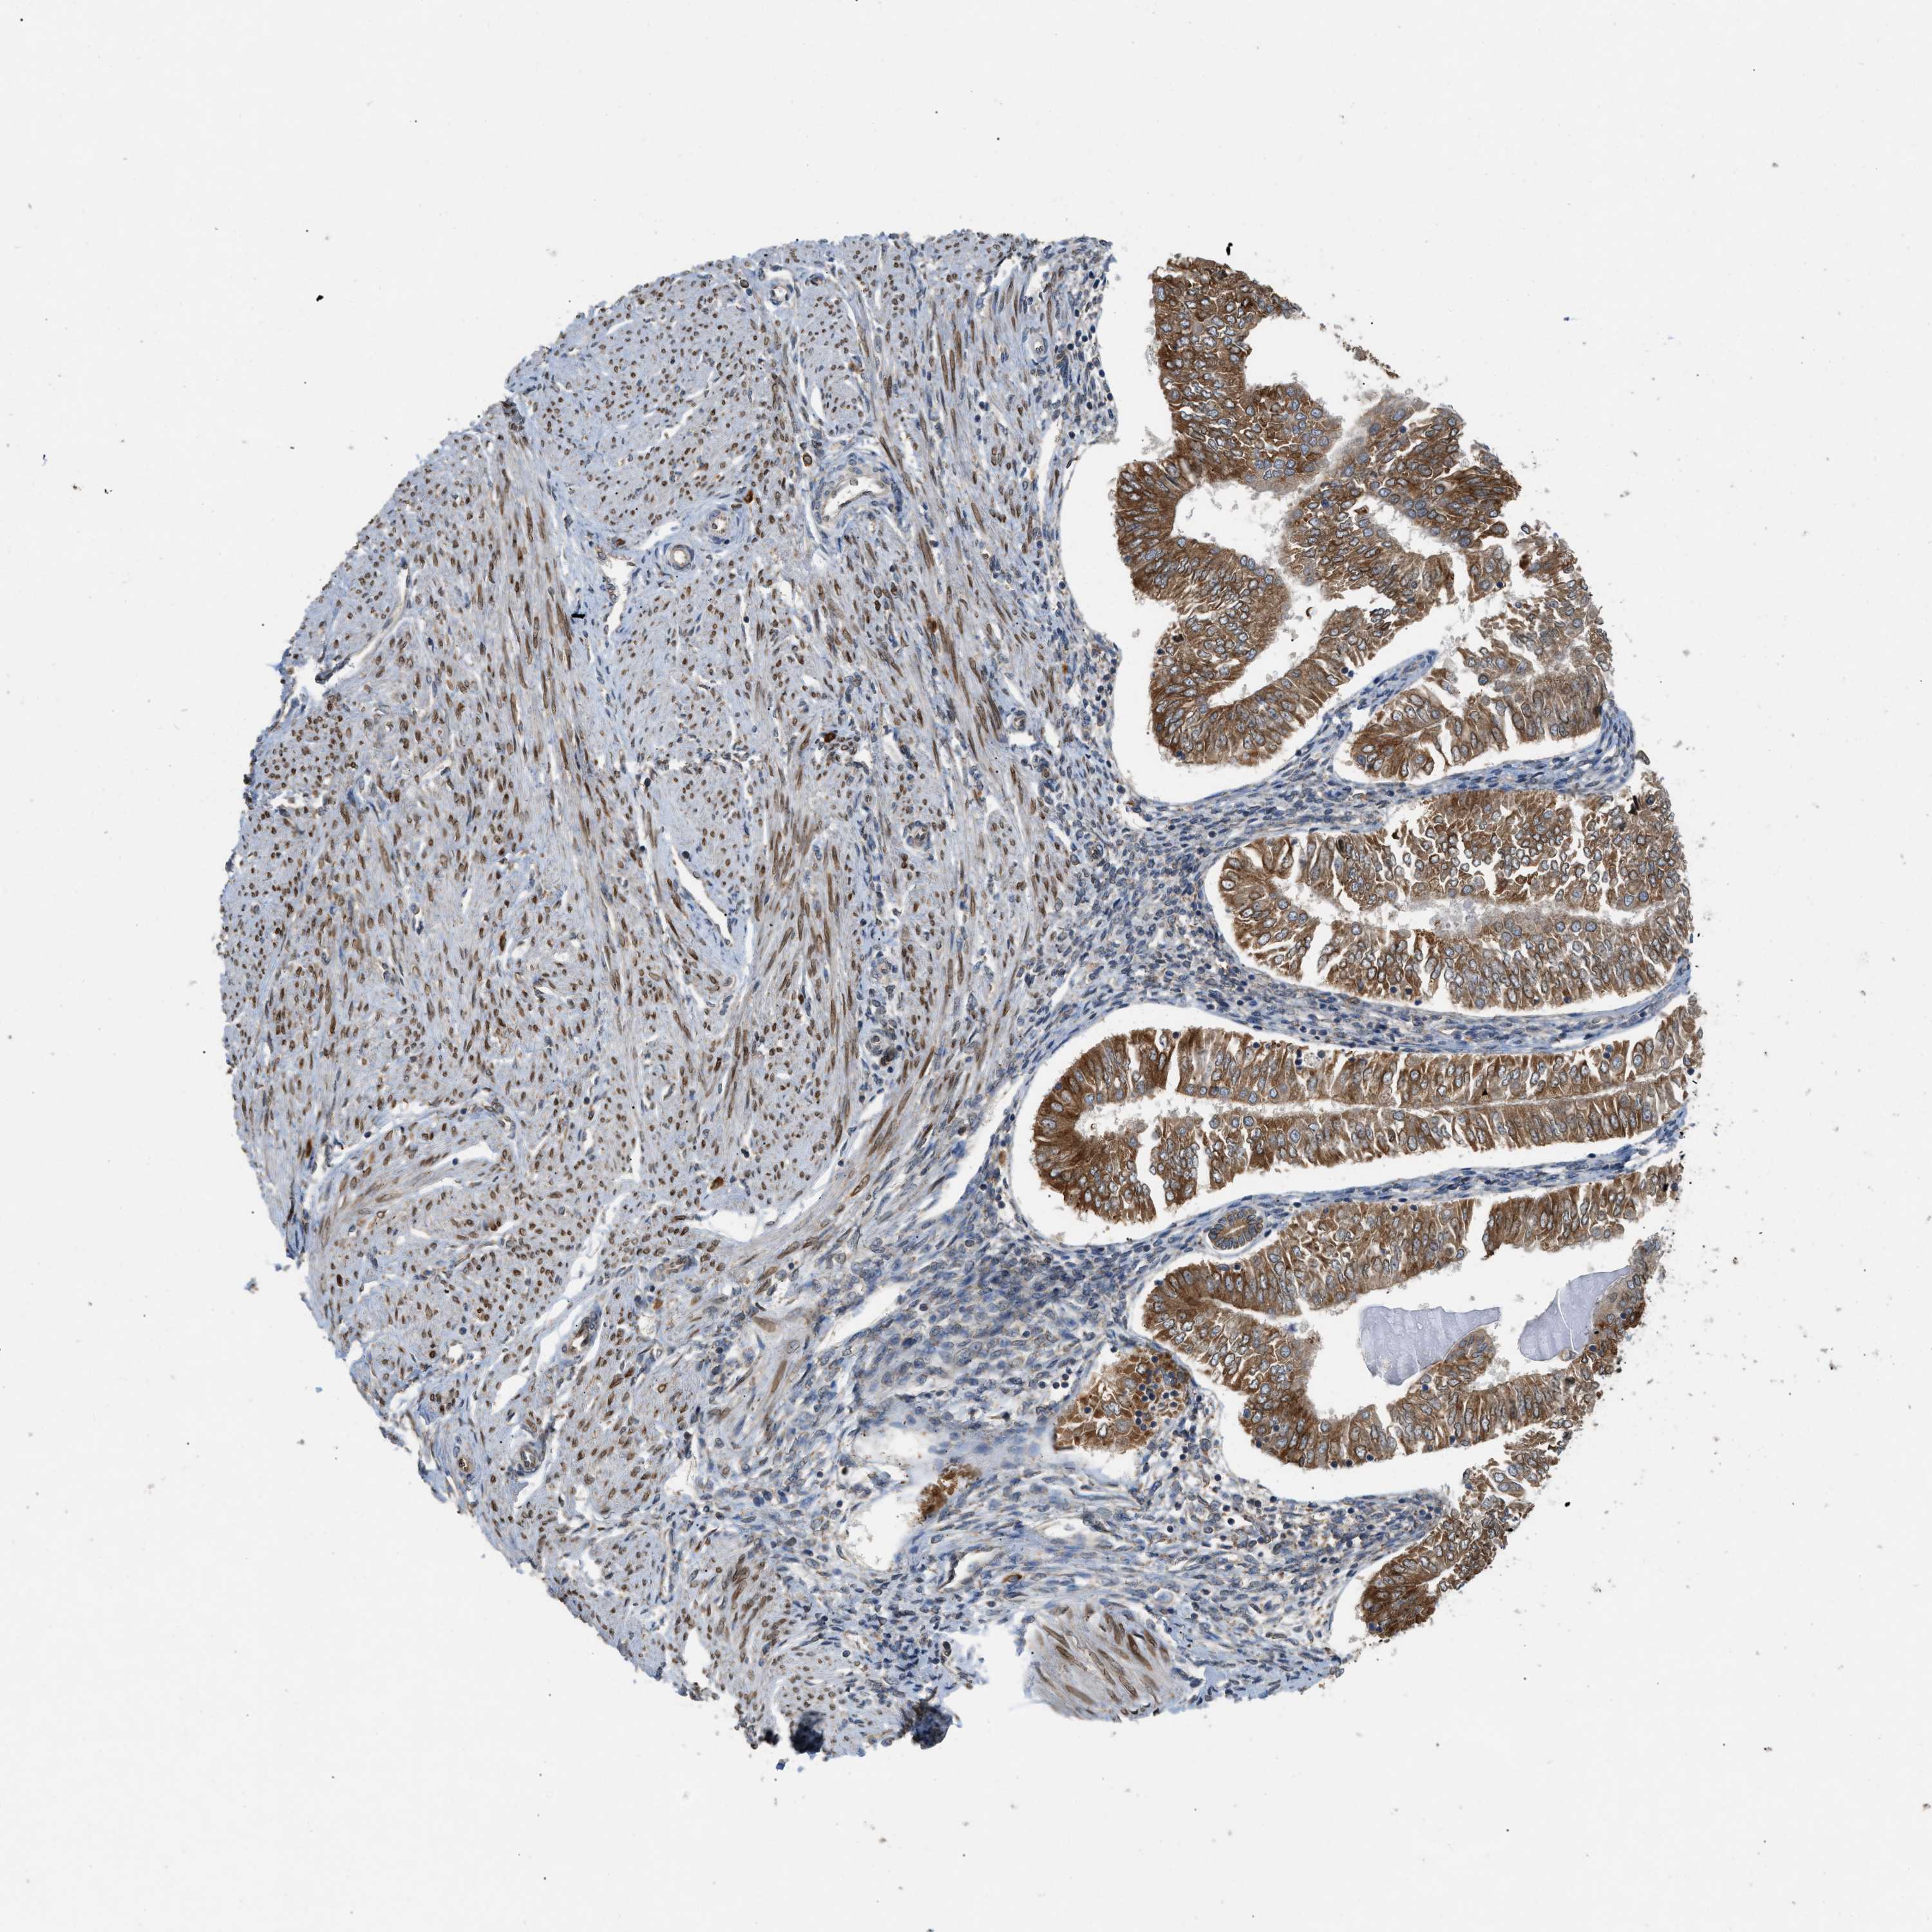

ENDOMETRIAL CANCER - Protein expressioni

A mouse-over function shows sample information and annotation data. Click on an image to view it in a full screen mode. Samples can be filtered based on level of antibody staining by selecting one or several of the following categories: high, medium, low and not detected. The assay and annotation is described here.

Note that samples used for immunohistochemistry by the Human Protein Atlas do not correspond to samples in the TCGA dataset.

Antibody stainingi

Antibody staining in the annotated cell types in the current human tissue is reported as not detected, low, medium, or high, based on conventional immunohistochemistry profiling in selected tissues. This score is based on the combination of the staining intensity and fraction of stained cells.

Each image is clickable and will lead to virtual microscopy that enables deeper exploration of all samples and also displays staining intensity scores, fraction scores and subcellular localization as well as patient and tissue information for each sample.

Antibody HPA014394

Staining

High

Medium

Low

Not detected

Intensity

Strong

Moderate

Weak

Negative

Quantity

>75%

75%-25%

<25%

None

Location

Nuclear

Cytoplasmic/membranous

Cytoplasmic/membranous,nuclear

Adenocarcinoma, NOS